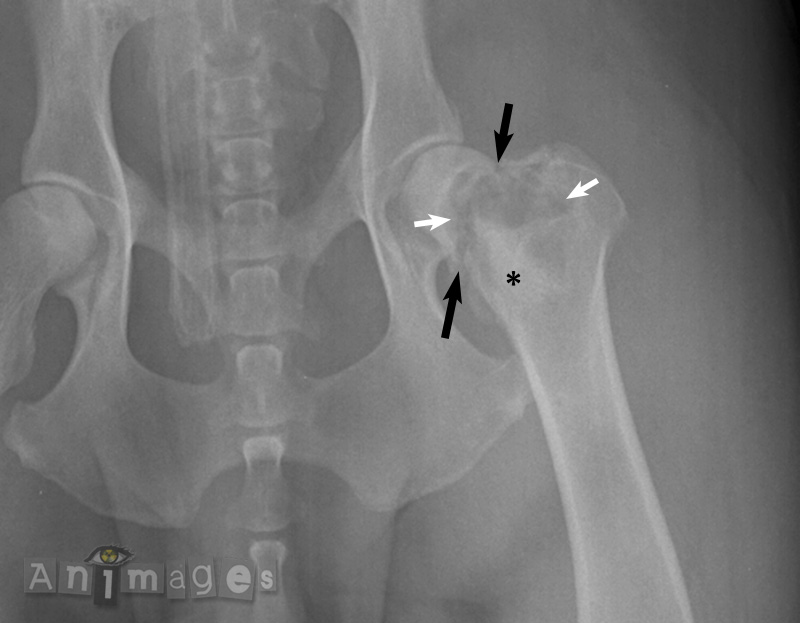

Il s’agissait en effet d’une lésion osseuse agressive. Celle-ci se caractérise par une zone de lyse mitée à géographique (flèches blanches) dans la métaphyse proximale du fémur, au contour mal défini et irrégulier, et accompagnée d’une prolifération osseuse mal définie superposée à la médulla à sa marge distale (*). La métaphyse est déformée et raccourci, alors qu’un défaut cortical est évident crânialement et caudalement (flèches noires), indiquant une fracture pathologique. Celle-ci est survenu en raison de la fragilité de l’os engendrée par le processus agressif. Les caractéristiques et la localisation de cette lésion, couplées au signalement et aux données cliniques de l’animal, sont compatibles avec une tumeur osseuse maligne primaire (ostéosarcome, fibrosarcome ou chondrosarcome) ou encore une tumeur d’une autre lignée cellulaie, tel un sarcome histiocytaire. Techniquement, une ostéomyélite aurait pu être considérée sur la base de cette image, mais collait moins bien avec l’histoire clinique et la loi des chiffres (i.e. la probabilité de rencontrer une ostéomyélite chez un animal mature, dans la métaphyse fémoral proximale, comparativement à une tumeur osseuse primaire). Un ostéosarcome a finalement été confirmé.